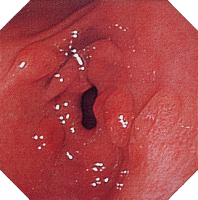

上部消化管病変(1) 上部消化管病変(2) 上部消化管病変(3)

クローン病画像 クローン病画像 クローン病画像

提供:牧山和也先生